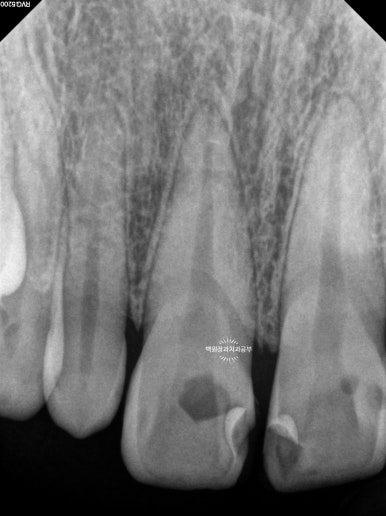

얼마나 충치가 진행되었는지 눈으로만 확인하지 않습니다.

치근단 사진을 촬영하여 보다 자세히 살펴볼 수 있었습니다.

눈으로 보는 것과 같은 위치입니다만, 엑스레이로 보았을 때 현재 위치하는 충치가 치아 내부의 신경관과 얼마나 가까이 위치하는지를 확인할 수 있었습니다.

이에 가장 충치가 심했던 측절치는 신경치료를 할 가능성이 아주 높으며 기둥을 설치해야 한다는 정보를 얻을 수 있었습니다.